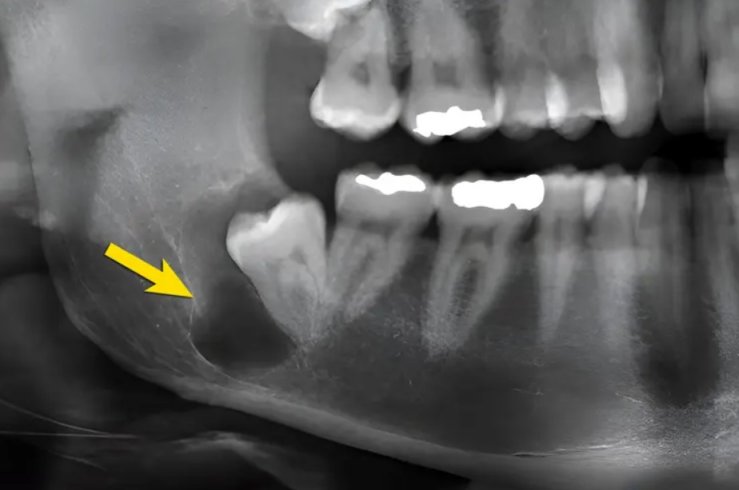

- одонтогенні пухлини — що походять із тканин зуба або його зачатка;

- неодонтогенні пухлини — що виникають із м’яких тканин або кістки;

У складних випадках застосовується комп’ютерна навігація, що дозволяє максимально точно визначити межі ураження й уникнути травм здорових структур.

Щелепно-лицеві травми — одна з найчастіших причин госпіталізації. Це можуть бути переломи нижньої або верхньої щелепи, виличної дуги, носових кісток. У лікарні ім. І. І. Мечникова застосовуються найсучасніші методики фіксації — остеосинтез із використанням титанових пластин і гвинтів, що забезпечує точне зрощення кісток без порушення естетики обличчя. Пацієнти після таких операцій швидше повертаються до звичного життя, не потребують тривалого знерухомлення щелеп.